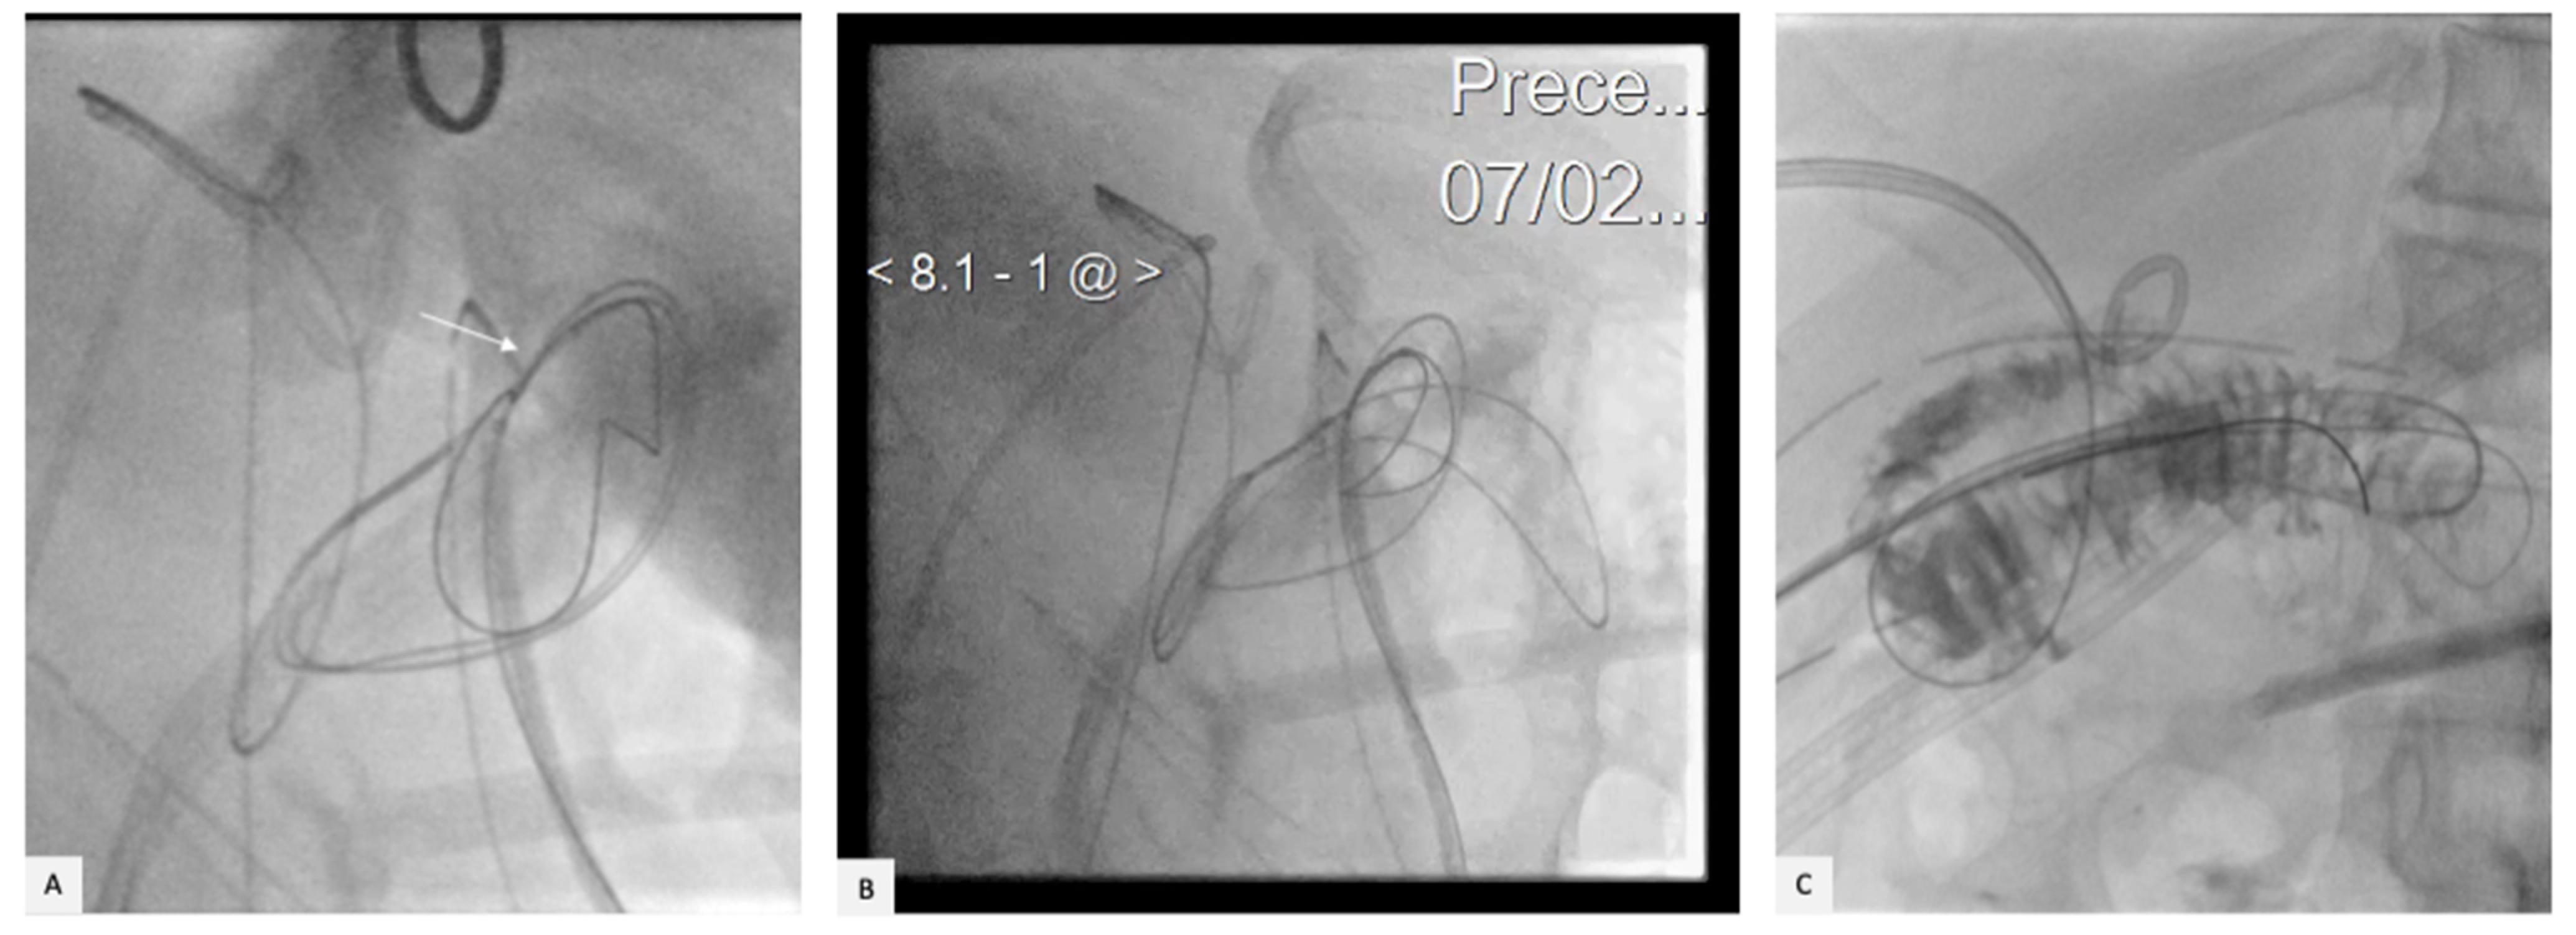

2. Case Presentation